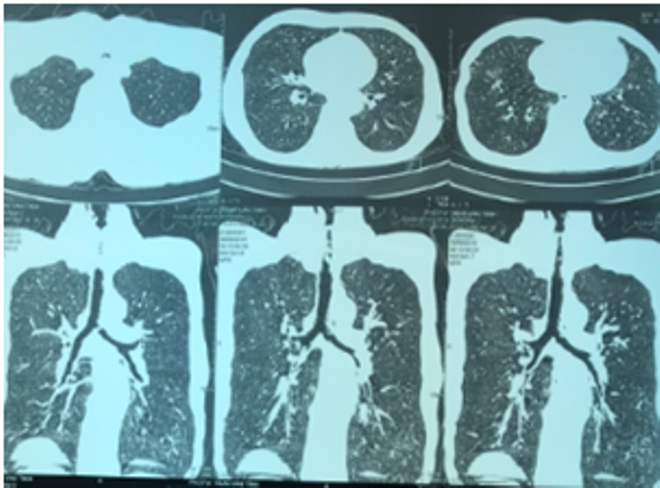

Cứu sống một bệnh nhân bị suy hô hấp cấp do hẹp khí quản ảnh 1Hình ảnh chụp CT ngực của bệnh nhân cho thấy có tình trạng hẹp khí quản ở đoạn 1/3 trên. (Ảnh: BV cung cấp)

Bệnh nhân đã được chụp CT scanner ngực có hình ảnh hẹp khí quản, được nội soi phế quản cấp cứu phát hiện thấy có tình trạng xơ sẹo gây chít hẹp gần hoàn toàn khẩu kính khí quản đoạn 1/3 trên, ngay dưới thanh môn. Tình trạng hẹp khí quản mức độ nặng này có nguy cơ đe dọa tử vong ngay cho người bệnh.